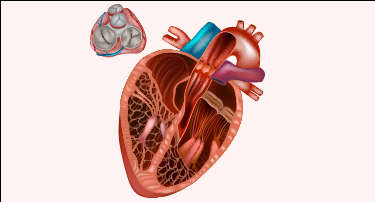

What Is Structural Heart Disease? Symptoms, Causes & Modern Treatment Options

Think of your heart as your “home” with multiple rooms, doors, a water pipe supply, and other structural systems, working together perfectly to keep it running.

Exploring Valvular Heart Disease: Causes, Symptoms, and Treatments

Valvular heart disease is among the most prevalent heart disorders in today's scenario. Patients with this disorder may suffer from life-threatening complications, severe limiting symptoms, and a shorter lifespan.